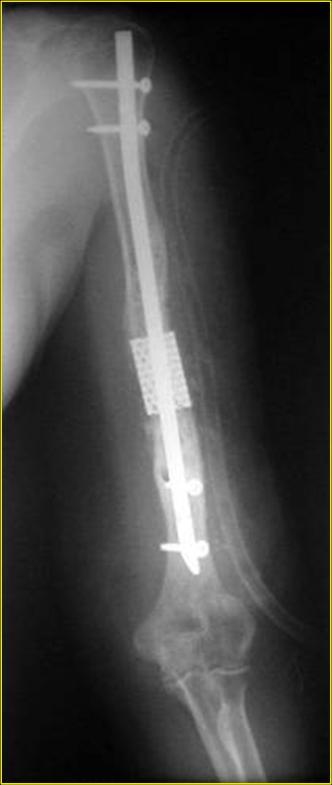

Типичная положительная ситуация для интрамедуллярного остеосинтеза с

использованием опорного металлокаркаса для компенсации дефекта.

Рентгеновская версия реконструкции. хронология:

после операции, 2 мес. после операции, через 1 год